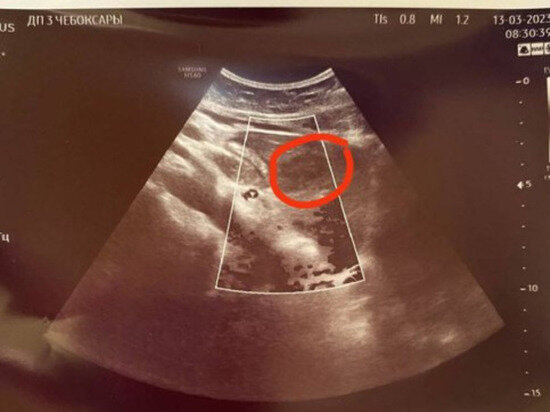

Чебоксарские врачи обнаружили у подростка новообразование на диспансеризации

Новообразование удалось обнаружить у ребенка при диспансеризации врачам ультразвуковой диагностики Городской детской клинической больницы Чебоксар. Диаметр опухоли 20-25 мм, врачи еще не знают злокачественная ли она. Пациентке рекомендовали пройти дальнейшее обследование у хирурга и онколога, также необходимо пройти компьютерную томографию с усиленным контрастом. Это уже второй случай с начала текущего года, ранее было обнаружено образование в головке поджелудочной железы у подростка, и тоже во время диспансеризации. Подобные случаи дают ясно понять необходимость своевременного обследования у детей и взрослых. Ежегодный осмотр позволит выявить аномалии на ранних этапах и позволит спасти жизнь. О важности обследования сообщает Минздрав Чувашии. Автор: Николай Новоселов